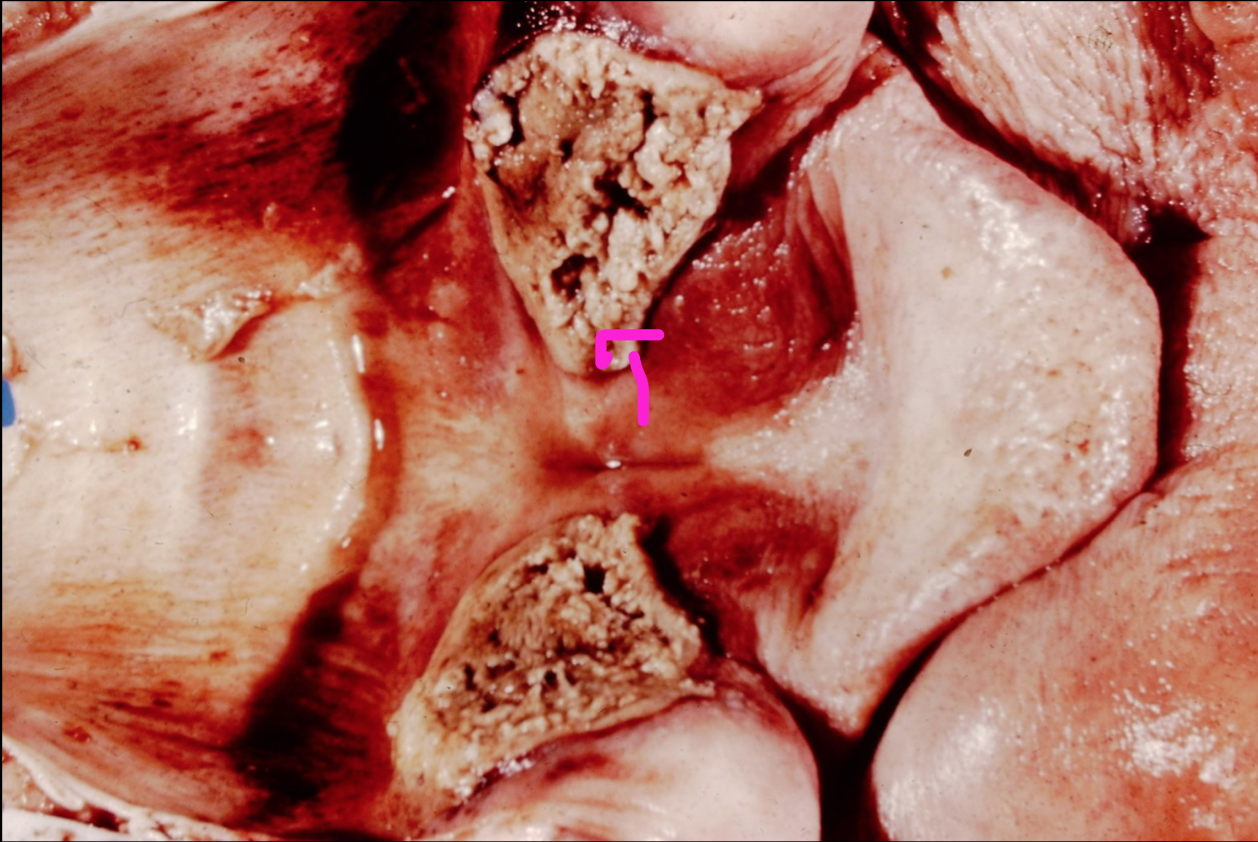

Acute multifocal necrotizing laryngitis

septicemic histophilus

Chronic local extensive necrotizing laryngitis

necrobacillosis